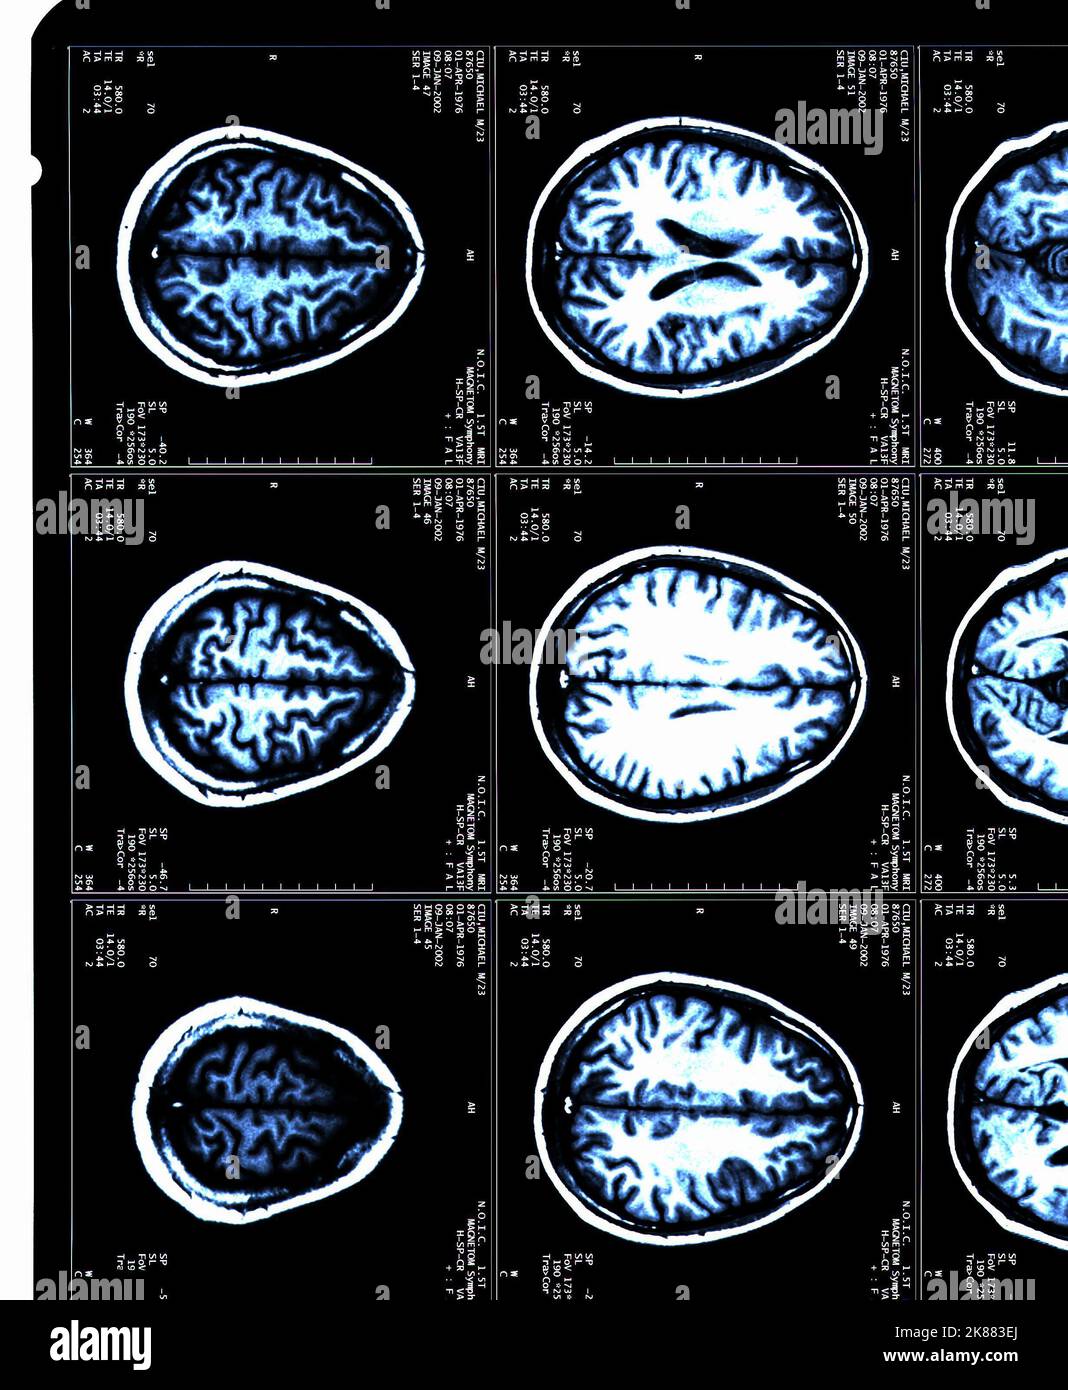

From www.alamy.com

Healthy brain and brain with amyloid plaques, MRI scans Stock Photo Alamy Plaque In Brain On Mri white matter disease refers to changes in the brain's white matter, the part of the brain responsible for communication between different brain regions. White matter lesions are one of the most common. while experts may not be able to confirm cerebral amyloid angiopathy before death, they can still make a highly probable. — mayo clinic researchers led a. Plaque In Brain On Mri.